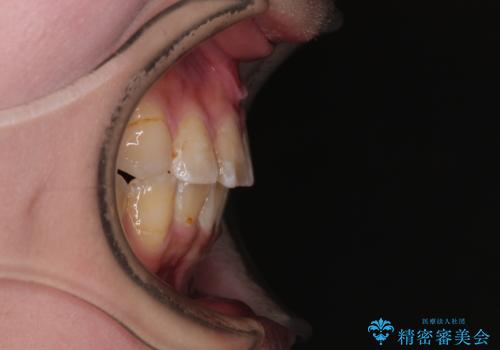

重度叢生のため、大臼歯をしっかりと咬合させるために、下顎は左右第二小臼歯を、上顎は前歯部の叢生を解消するために左右第一小臼歯を抜歯し、口元の突出感を改善するために、上顎大臼歯が前方に移動しないようにするために、補助装置による架強固定を行うこととしました。

叢生は思ったよりも早期に改善されましたが、舌の突出癖による上下前歯の非接触が全く改善されず、2年間ほど治療期間が延びる結果となってしまいました。